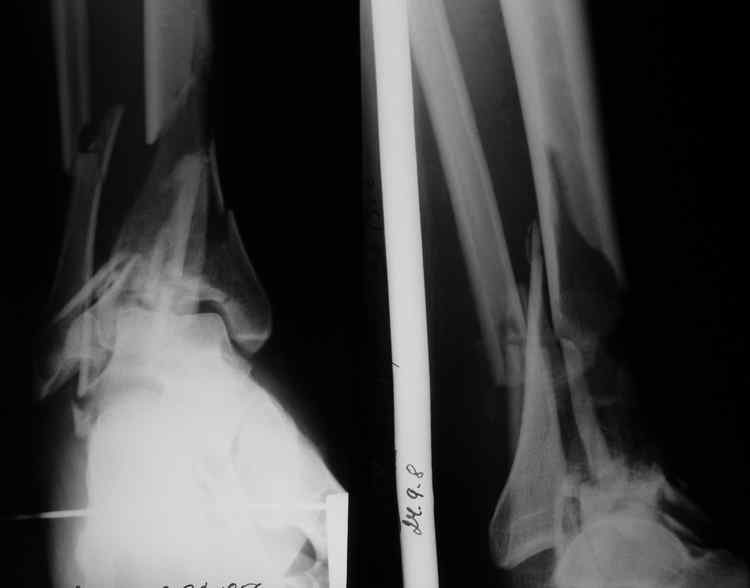

Re: Тяжелый перелом пилона